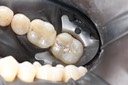

Wayne Chin #30 pre-op

Wayne Chin #30 prep

Wayne Chin #30 finish